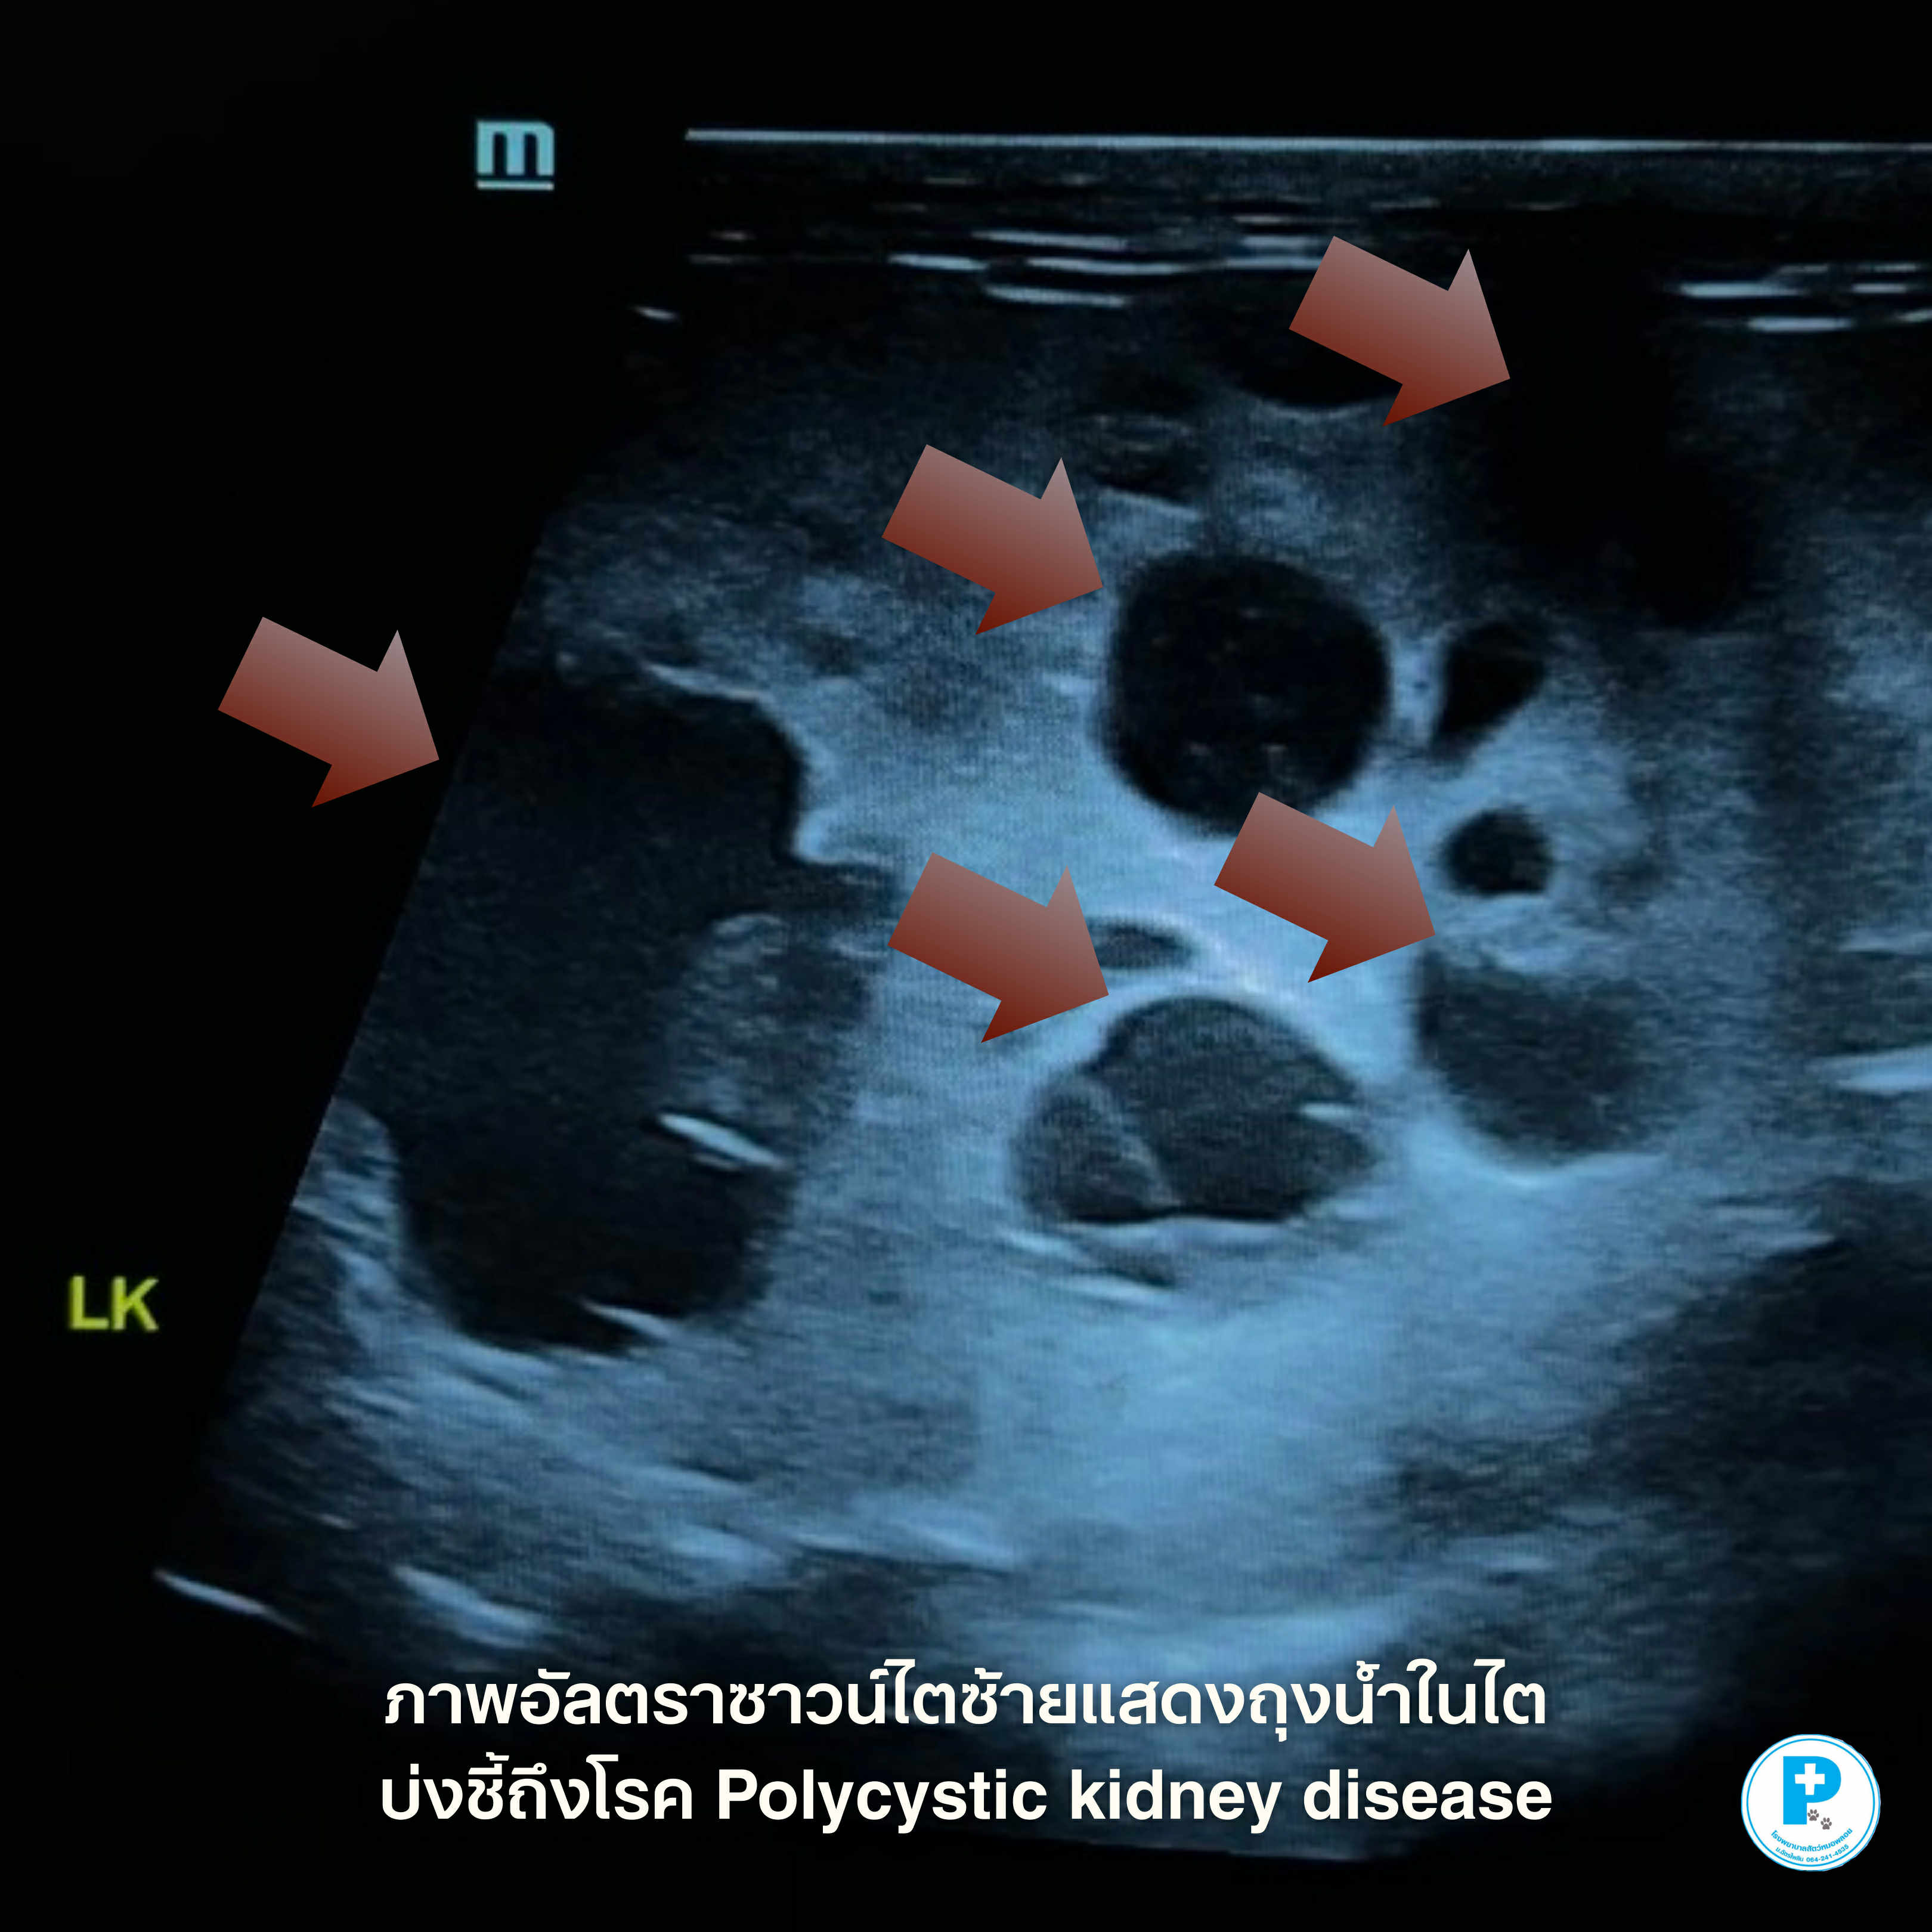

น้องแมวชื่อเทามาตรวจสุขภาพประจำปี ผลตรวจเลือดปกติ ร่าเริง กินได้ เล่นได้ ไม่มีอาการป่วยใด ๆ แต่จากการ อัลตราซาวนด์ช่องท้อง พบว่าไตซ้ายมี ถุงน้ำหลายใบ วินิจฉัยได้ว่าเป็น “โรคถุงน้ำในไต (Polycystic Kidney Disease: PKD)”

🔍 PKD คืออะไร?

PKD เป็นโรคทางพันธุกรรมในแมว ทำให้เกิดถุงน้ำหลายใบภายในเนื้อไต ถุงน้ำจะค่อย ๆ โตขึ้นตามเวลา และอาจส่งผลต่อการทำงานของไตในระยะยาว

อัลตราซาวน์/เรียบเรียง: น.สพ.นรภัทร โสภิพันธ์ (หมอพีท)